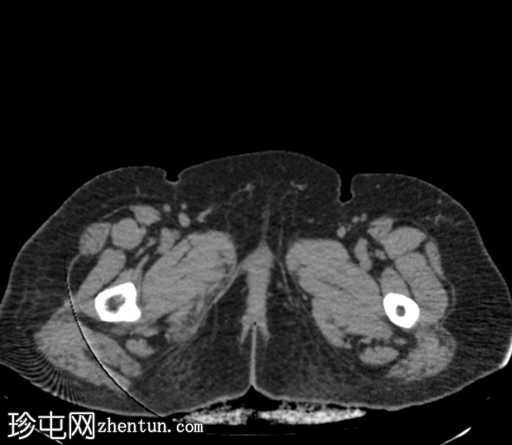

CT

轴位

平扫

轴位肾皮质期

轴位肾排泄期

冠状位肾排泄期

矢状位肾排泄期

右肾中度肾积水,输尿管积水延伸至S4椎体水平。延迟期图像显示阴道残端扩张并充满造影剂,与右侧远端输尿管相通。

平扫图像显示左侧肾盏系统内有残留造影剂。

延迟期图像显示右侧肾盂呈斑片状强化,提示延迟性肾图,可能由远端梗阻引起。